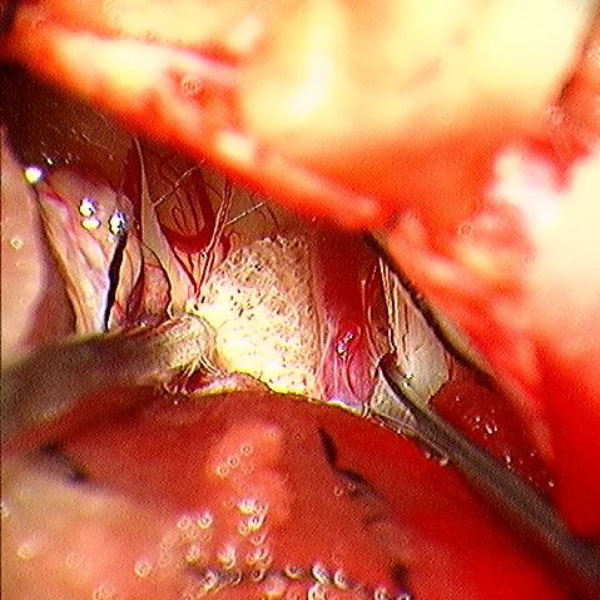

手術中

処置前

処置後